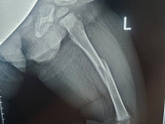

12 октября 2023 18:03 +1 Вот так ,строишь планы ,бегаешь как белка в колесе ,покупаешь билеты отдыхать... А потом бац!и перелом бедра у ребенка,на ровном месте ,просто шел и упал ,все! Операция прошла быстро и вроде хорошо Теперь никаких планов ....даже никаких сроков . Лежим … Читать далее

11 октября 2023 21:09 Сделали операцию......??? Три недели теперь так лежать нам с ним Ни шагу вправо или влево ,всегда подвешена нога .... Потом после сращивания ещё гипс 3 недели Девочки.... это кошмар. Спасибо ГВ нашему ,хоть это сейчас ему чуть помогает (((((

11 октября 2023 17:31 Девочки это просто Пииииииз@деееееец К предыдущему посту Писать не могу много ,едем в скорой помощи в детскую травму ,у нас на районе нет детской хирургии травматалогии.... В общем приехала я в травму у нас ,а у малого Перелом бедра мать его … Читать далее

11 октября 2023 15:00 Есть тут такие у кого у малышей был Вывих или перелом ??? Бежал только что мой маленький дома и подскользнулся на ровном месте и нога ушла в бок ,плакал долго и держался за колено,пока не уснул на руках ???я теперь лежу с ним и переживаю....вдруг это … Читать далее